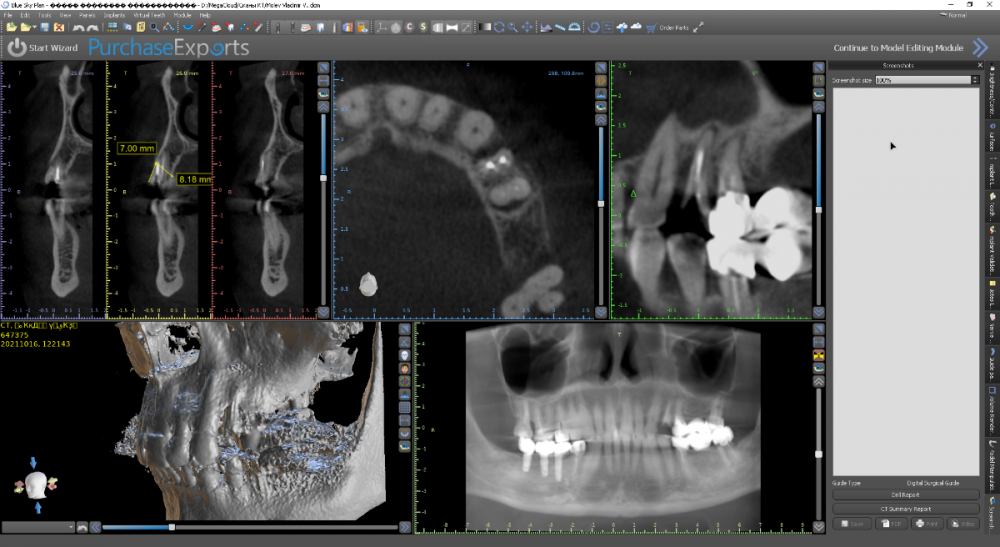

Женька Опубликовано 17 октября, 2021 Поделиться Опубликовано 17 октября, 2021 Перелом под десну, рядом мост 2.5-2.7, который конечно же пациент менять не хочет. Смущает дефект между клыком и 2.4, переходящий на вестибулярную пластинка 2.4. Как решали бы? Возможно только мягкими тканями закрыть? Пошли бы одномоментно или законсервировали бы? Ну и ангуляция имплантата, приемлемое ли положение для ортопедии выходит? Ссылка на комментарий

Женька Опубликовано 19 октября, 2021 Автор Поделиться Опубликовано 19 октября, 2021 Коллеги, срезы неверные или не хватает информации? Или слишком банальные вопросы и раз я их задаю, значит лучше не стоит лезть и поэтому никто ничего не советует? Ссылка на комментарий

Irouil Опубликовано 20 октября, 2021 Поделиться Опубликовано 20 октября, 2021 В 7 одномоментно по этим срезам проблем быть не должно 1 Ссылка на комментарий

Raystom Опубликовано 20 октября, 2021 Поделиться Опубликовано 20 октября, 2021 @Irouil мне показалось, что есть большой карман дистально и без пластики невозможно установить имплантат Ссылка на комментарий

Irouil Опубликовано 20 октября, 2021 Поделиться Опубликовано 20 октября, 2021 6 часов назад, Raystom сказал: @Irouil мне показалось, что есть большой карман дистально и без пластики невозможно установить имплантат Есть карман, но в отсроченном варианте что изменится? Имхо после регенерации лунки лучше не станет Ссылка на комментарий